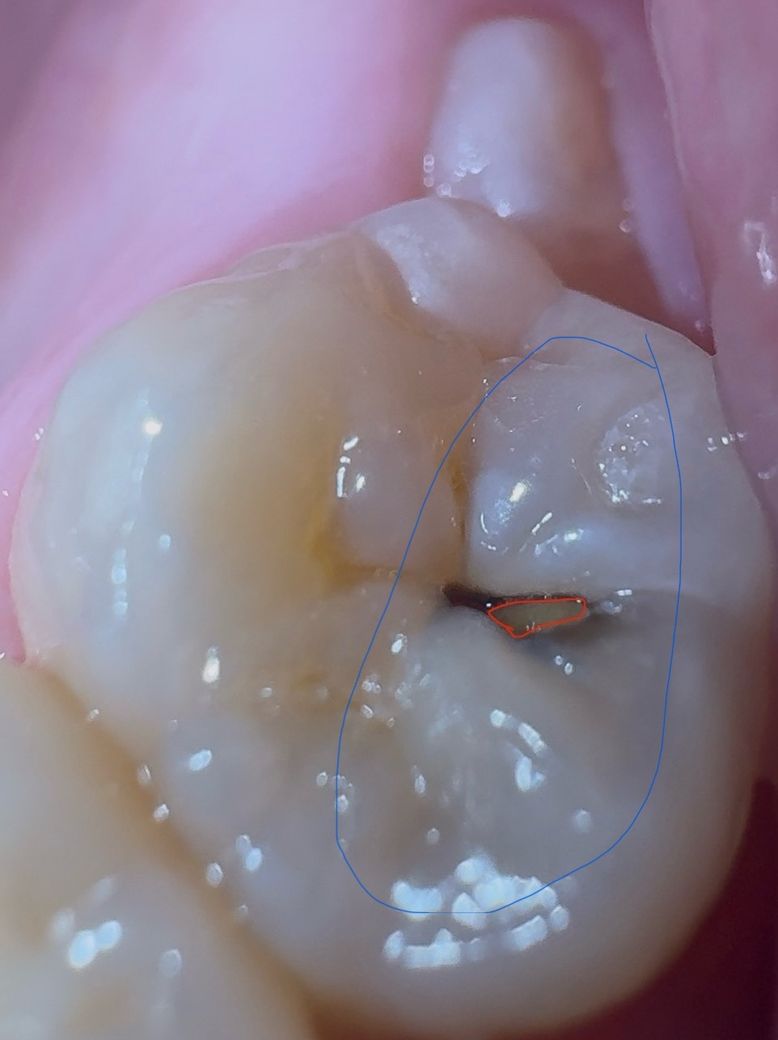

충치 주변 치아가 안쪽에서 검은색을 띄는 것을 보니

꽤 진행된 충치인 것 같아서 걱정되네요

파란색으로 표시한 부분이 약간 검은 것 같은데 저 부분도 내부는 충치인 건가요?

그리고 혹시 충치 사이에 노란색은 뭐죠?

빨간색으로 표시한 부분이요

이것도 그냥 치아인가요?